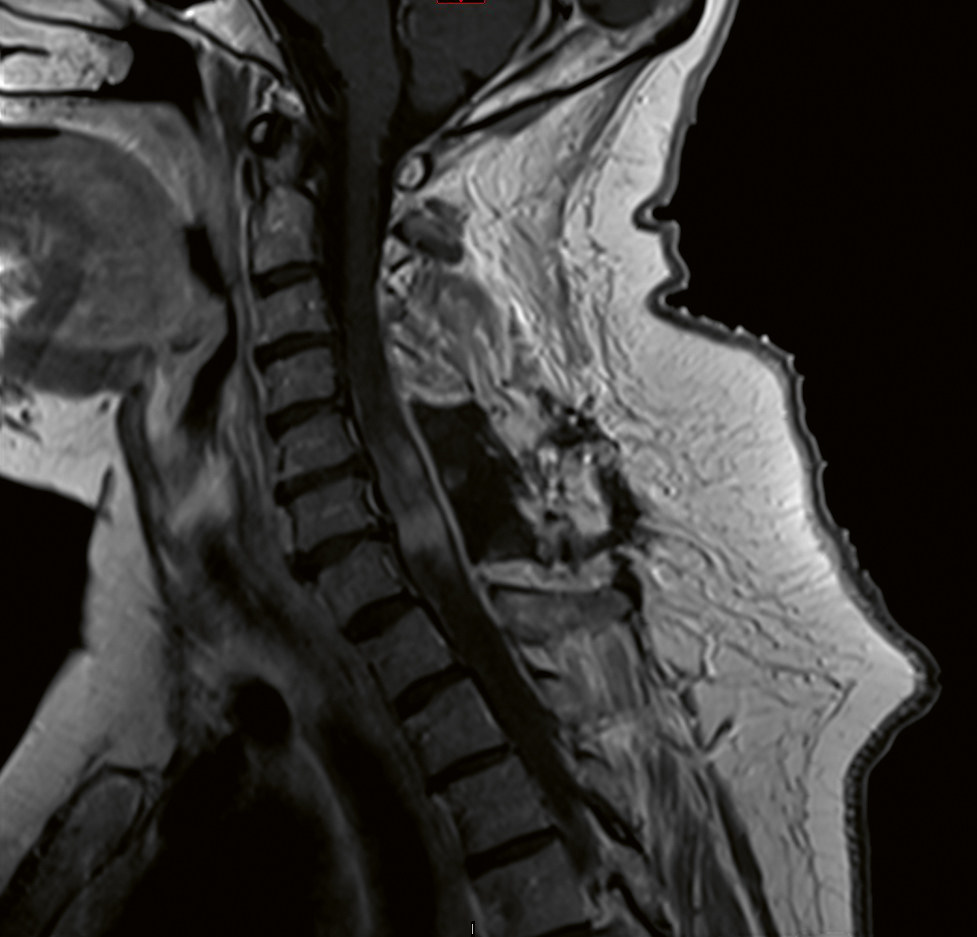

MR av ryggmärgen visar oftast leptomeningeala uppladdningar och kort- eller långsegmentmyeliter (Figur 4) [39]. Treuddstecken på axiala snitt kan användas för att särskilja neurosarkoidos från andra typer av myelit [40].

Figur 4. MR av ryggmärgen i halsryggsnivå, T1-viktad, Gd+. Bil­den visar utbrett ödem och kontrastuppladdning i nivå C4–C7.